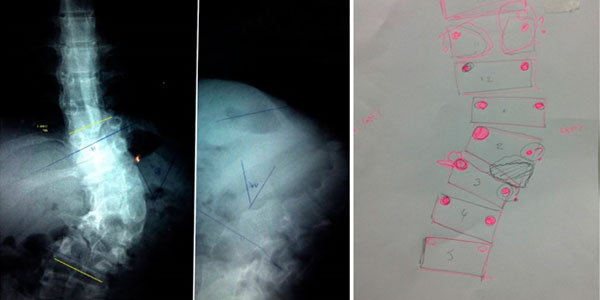

Cifosis rígida toracolumbar (Enfermedad de Scheuermann): varón de 20 años, consulta por dolor toraco lumbar intenso, realizo 4 anos de terapia física y rehabilitación sin éxito. 10 meses Post-operado, se tuvo que realizar varias osteotomías de columna, actualmente sin dolor, realiza actividades cotidianas sin limitaciones.